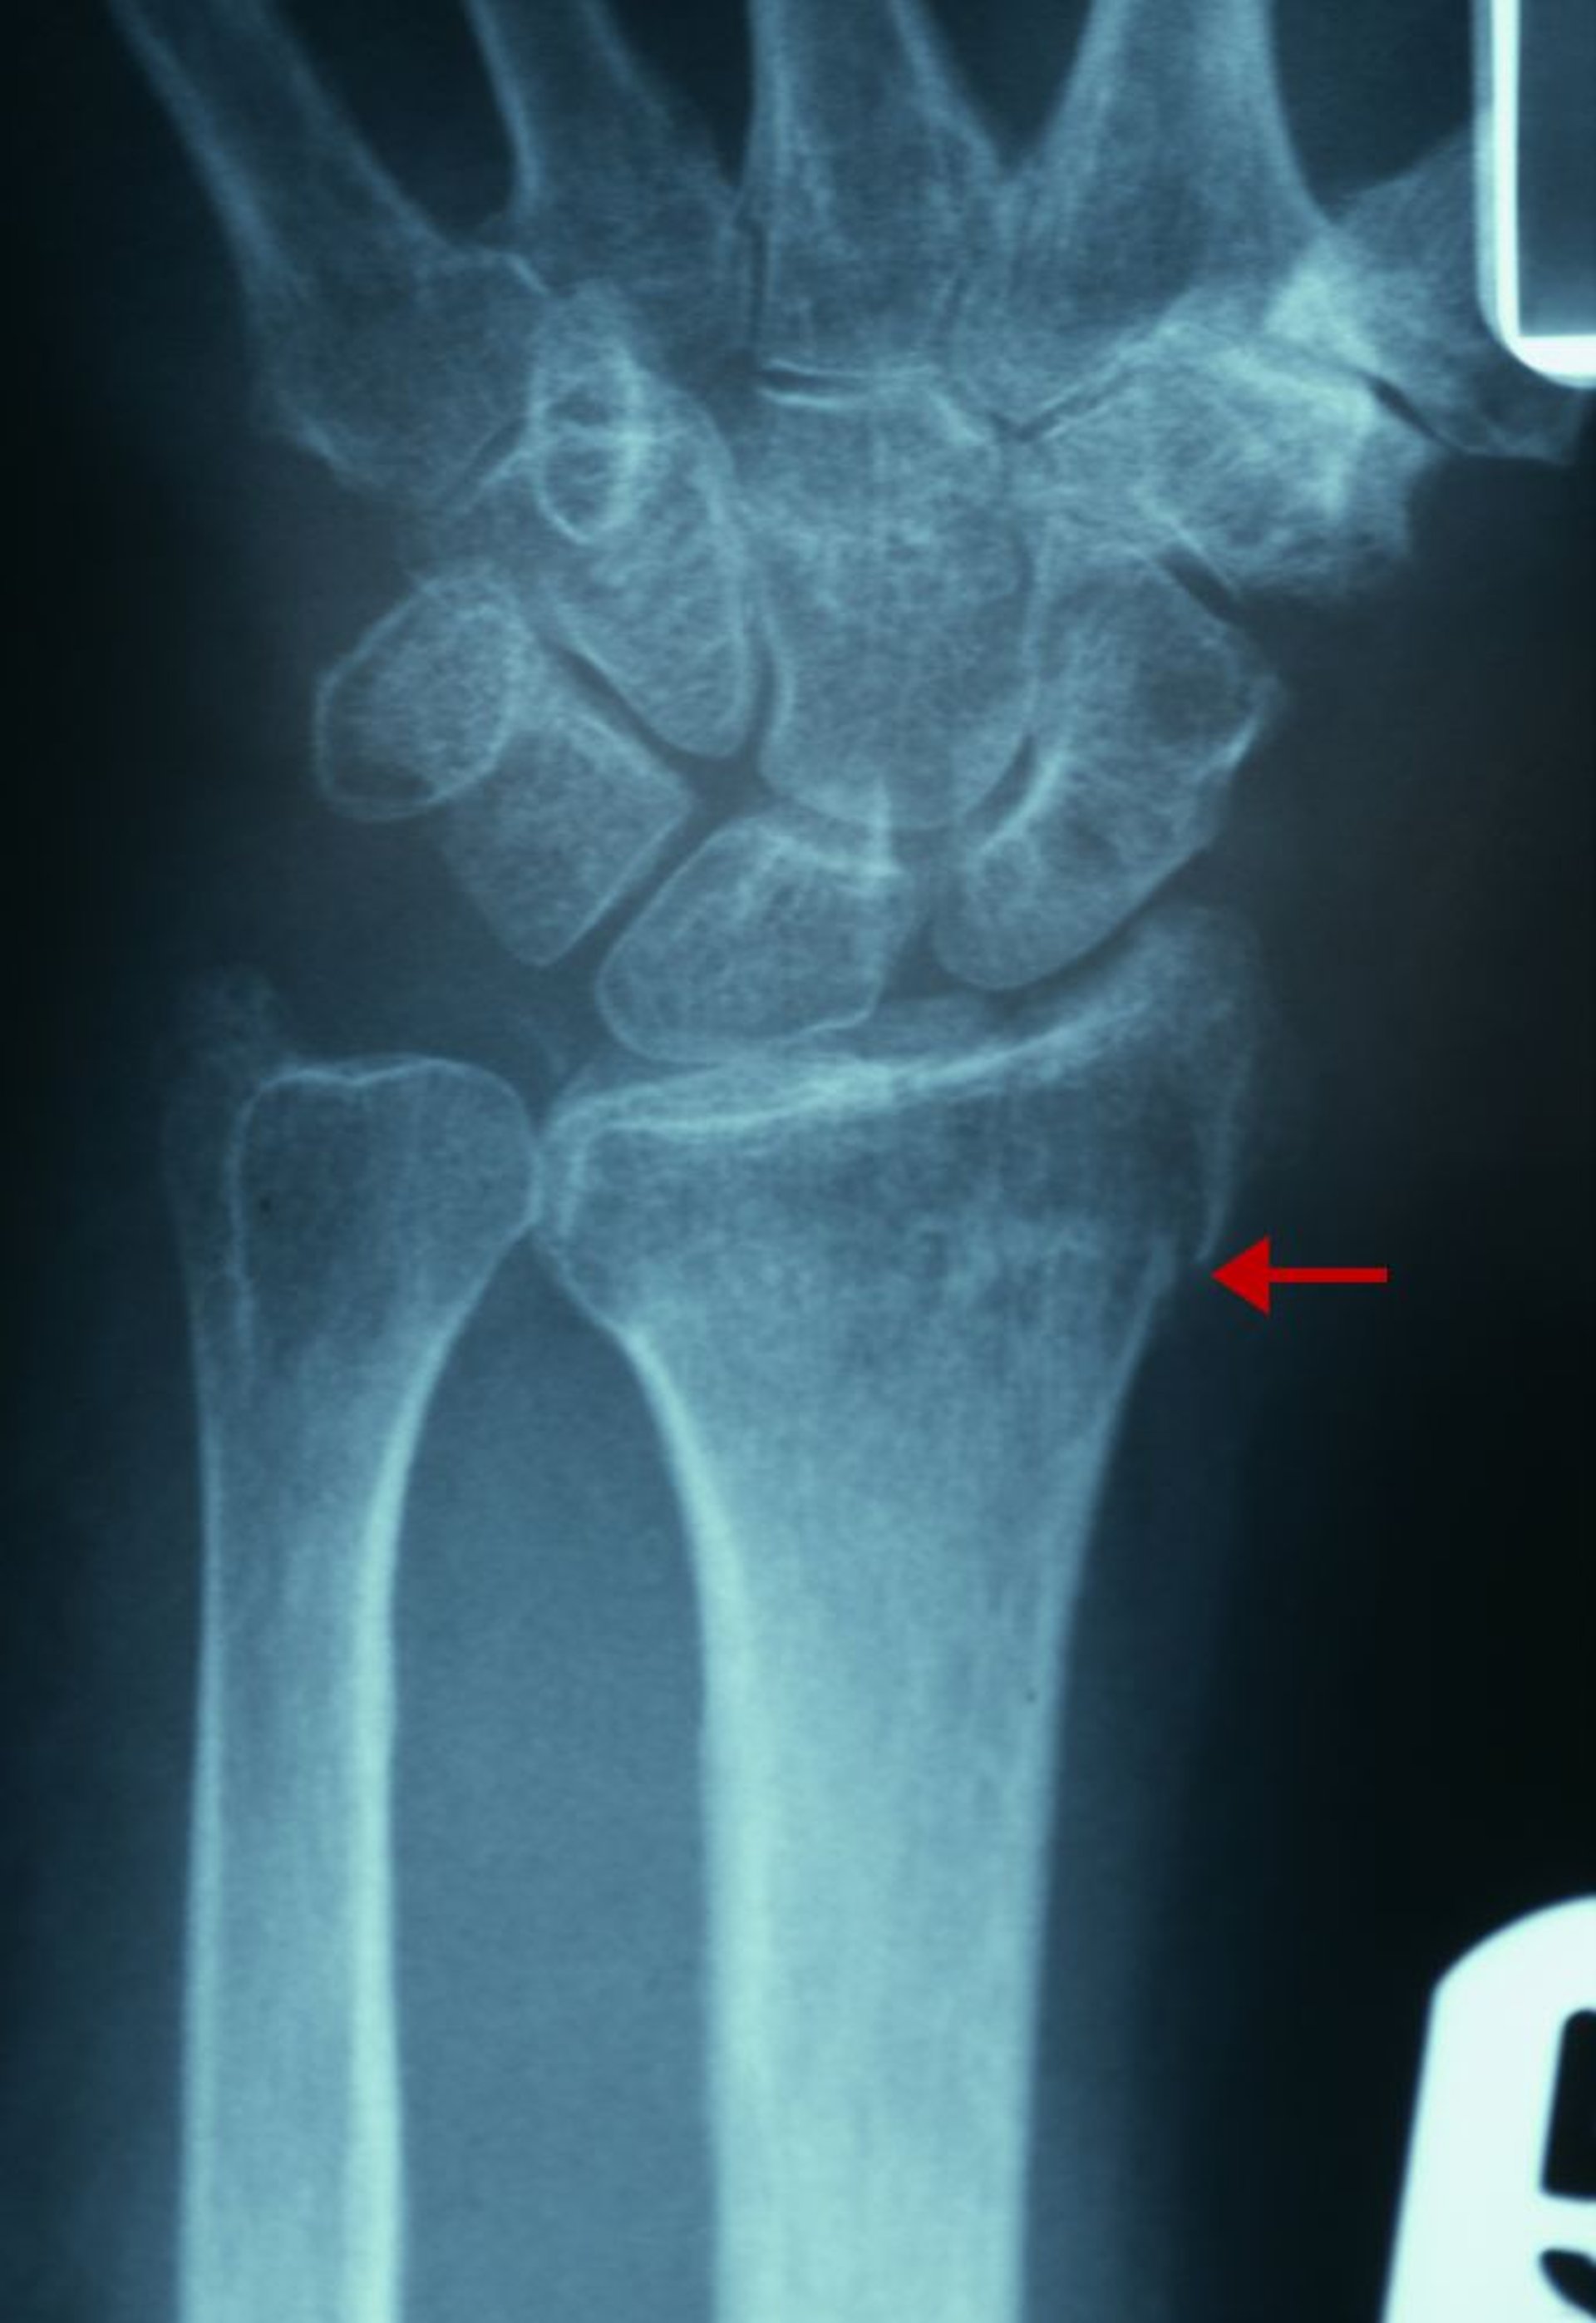

Frattura distale del radio sottile

L'evidenza radiografica di questa frattura comprende un'interruzione della continuità della corticale dell'aspetto radiale del radio distale (freccia) e un aumento della densità trabecolare del radio distale.